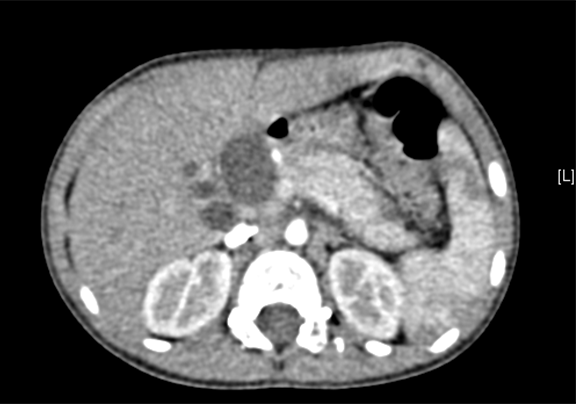

术前CT检查:

静脉期

上腹部动态三维成像(增强)CT:诊断意见:符合胆总管囊肿胆囊炎可能性大。